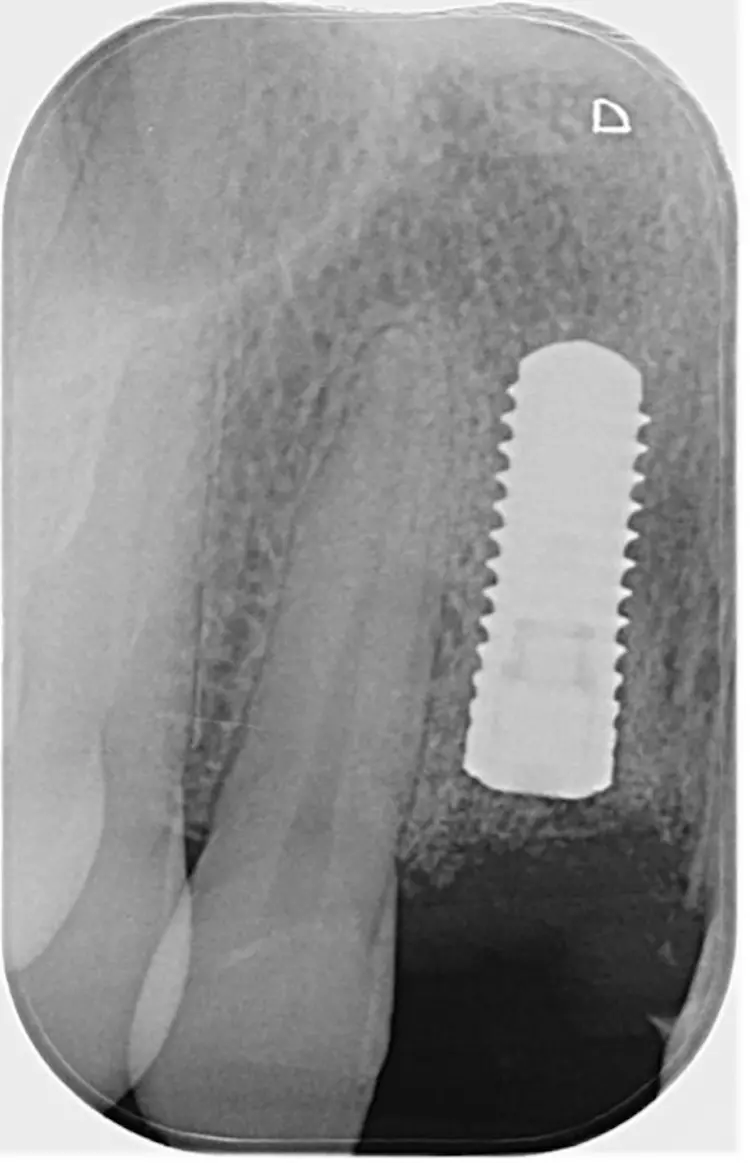

Nach einer viermonatigen Einheilzeit wurde im Rahmen der präimplantologischen Diagnostik ein DVT zur Überprüfung des Augmentationsergebnisses erstellt und die Implantatgröße festgelegt (Abb. 9 und 11). In Lokalanästhesie und unter Zuhilfenahme einer Bohrschablone erfolgte nach midkrestaler Schnittführung unter Schonung der Papillen die manuelle Insertion eines Straumann Bone Level Implantats mit den Maßen 4,1 x 10 mm RC (Straumann AG, Basel, Schweiz). Das Eindrehmoment betrug 35 Ncm.

Zahnklinik Bochum